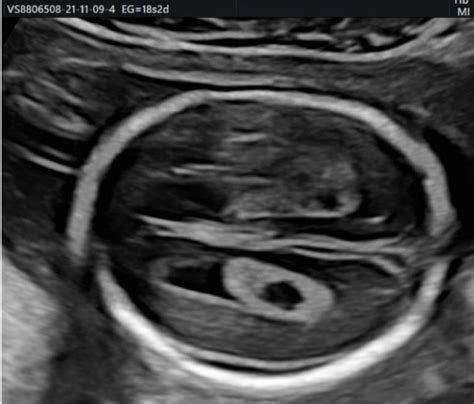

Un quiste del plexo coroideo se define como una pequeña bolsa llena de líquido que se desarrolla dentro del plexo coroideo del cerebro fetal. El plexo coroideo en sí mismo es una intrincada red de células y vasos sanguíneos ubicada en los ventrículos cerebrales, que son espacios llenos de líquido dentro del cerebro.

La formación de estos quistes ocurre cuando el líquido queda atrapado en las capas celulares del plexo coroideo, un proceso análogo a la formación de una ampolla bajo la piel.

La formación de un quiste del plexo coroideo puede comenzar alrededor de la sexta semana de gestación. Generalmente, estos quistes son detectados por los profesionales médicos durante una ecografía de rutina, habitualmente en el segundo trimestre del embarazo, alrededor de la semana 20.

Clásicamente, el tamaño de los quistes del plexo coroideo suele variar entre 3 y 16 mm. Es importante destacar que no existe una correlación directa entre el tamaño del quiste y el riesgo de anomalía cromosómica.

El hallazgo de quistes del plexo coroideo puede ser unilateral (en un solo lado) o bilateral (en ambos lados). Si los quistes son bilaterales, se considera especialmente importante revisar toda la morfología fetal, ya que existe una mayor asociación con anomalías cromosómicas.